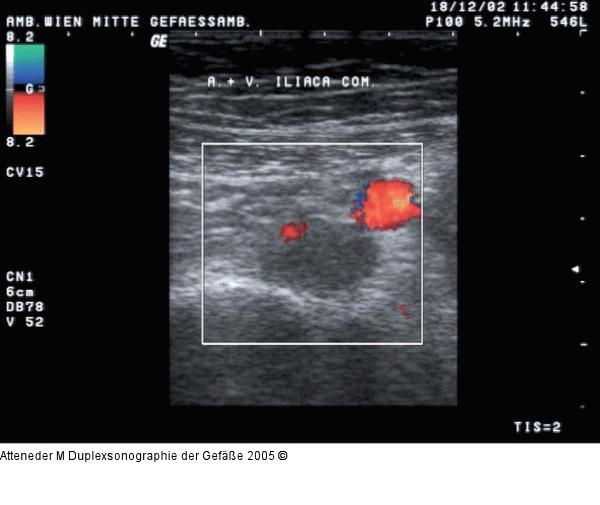

Abbildung 11: Duplexsonographie - Thrombose

Bei Thrombose Zunahme des Querdurchmessers der Vene im Vergleich zur Arterie |